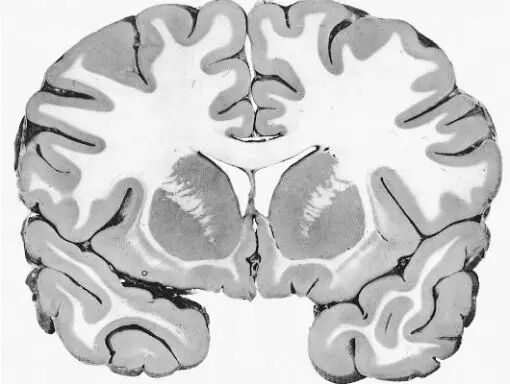

让我们使用半球横截面看看大脑的主要部分。因此,这是你脑袋里大脑的样子:

现在,让我们把大脑取出来,并删除左半球,这让我们能看清楚内部。